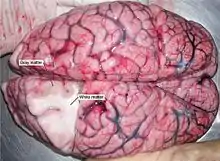

Dissection d'un cerveau démarquant la substance blanche de la matière grise.

Au microscope, il existe des différences entre les neurones, les tissus du système nerveux central et le système nerveux périphérique. Le système nerveux central est divisé en matière blanche (ou substance blanche) et matière grise[8]. Celles-ci peuvent aussi être observées macroscopiquement sur les tissus du cerveau. La matière blanche est constituée d'axones et oligodendrocytes, tandis que la matière grise est constituée de neurones et les fibres amyéliniques. Les deux tissus comprennent un certain nombre de cellules gliales, qui sont souvent désignées comme supportant les cellules du système nerveux central. Les différentes formes de cellules gliales ont des fonctions différentes, certains agissant presque comme échafaudage pour permettre aux neuroblastes de grimper au cours de la neurogenèse, tandis que d'autres tels que les microglies sont une forme spécialisée de macrophages, impliqués dans le système immunitaire du cerveau[3]. Les astrocytes peuvent être impliqués à la fois dans la clairance des métabolites ainsi que dans le transport de carburant et de diverses substances bénéfiques pour les neurones du cerveau.

Le cerveau (comportant le cervelet ainsi que la mésencéphale et le rhombencéphale) se compose d'un cortex, composé de neurones constituant la matière grise, tandis qu'à l'intérieur, il y a plus de matière blanche. En dehors de la matière grise du cortex[8].